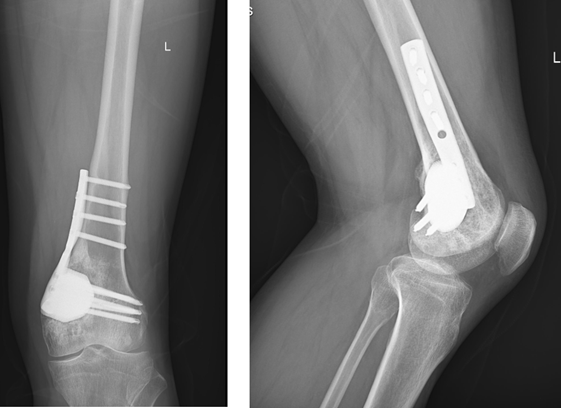

术中本以为在3D技术可以精准的匹配患者骨缺损区域,但患者骨质畸形,其解剖标志、内部结构都异于常规,最终克服重重困难,成功植入3D打印假体,并通过外接钢板固定方式将假体和自体骨连接一体。患者的成功救治离不开数智医学的有力加持。3D打印技术对伤病造成的巨大骨缺损问题,一方面解决了骨缺损修复重建术中内植物的个体化定制,更为重要的是内植物可被加工成微孔结构以供骨组织长入,微孔结构内长入骨组织就意味内植物可以与相邻骨骼实现有效融合,这一特性在此类骨科疾病治疗中至关重要。

术后一个月患者佩戴膝关节支具下地行走,术后2个月患者不佩戴任何支具自由活动,生活完全自理。术后3个月,患者完全回归正常工作,可以远足、登山。术后至今已达1年,更长期的随访结果仍在继续。影像学检查示3个月时即可看到假体两端周围的较多量骨组织包绕,随时间延长,内植物周围骨包绕的征象越来约明显。

术后1年随访:摄片示假体和自体骨骼整合较好,患者膝关节功能完全正常,VAS评分0分。